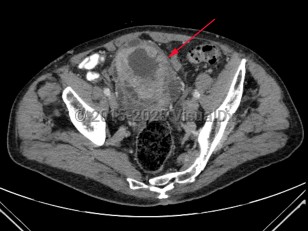

Patients with bladder cancer typically present with painless gross or microscopic hematuria, although dysuria, frequency, and urgency may be the presenting symptoms. Diagnosis may be delayed due to the similarity of these symptoms to benign conditions such as urinary tract infections, nephrolithiasis, cystitis, or prostatitis. Urothelial cancer may mimic bladder cancer. In patients younger than 50 years, asymptomatic microscopic hematuria is rarely associated with bladder cancer.